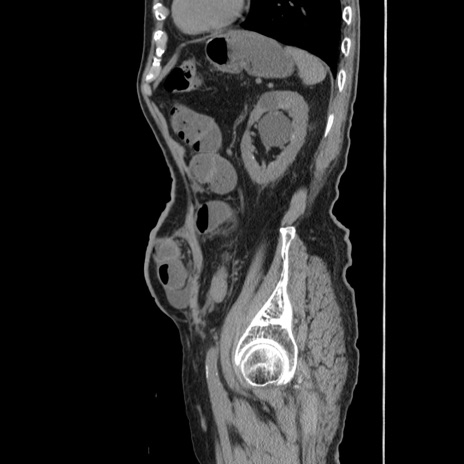

症例24(矢状断像)

【症例】80歳代男性

【主訴】左側腹部痛、嘔吐

【現病歴】本日早朝より左腹部に痛みあり。昼頃嘔吐認めたため、救急要請。

【既往歴】直腸癌(Mile手術)、胆摘

【身体所見】意識清明、BT 35.9℃、BP 221/93mmHg、SpO2 97%(RA) 、腹部:左ストーマ周囲に限局性の腹部膨隆あり。 膨隆部自発痛・圧痛あり・軟。

【データ】WBC 7700、CRP 0.09